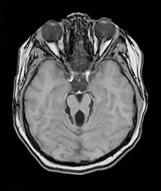

一歲男童有發展遲緩及低張力,腦部磁振照影出現特別的臼齒症狀(molar tooth sign)

Joubert 症候群